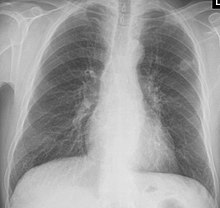

In der Medizin dient das Röntgen zur Feststellung von Anomalien im Körper, die im Zusammenhang mit Symptomen, Zeichen und eventuell anderen Untersuchungen eine Diagnose ermöglichen (Röntgendiagnostik). Die unterschiedlich dichten Gewebe des menschlichen (oder tierischen) Körpers absorbieren die Röntgenstrahlen unterschiedlich stark, so dass man eine Abbildung des Körperinneren erreicht (Verschattung, Aufhellung und andere Röntgenzeichen). Das Verfahren wird zum Beispiel häufig bei Verdacht auf einen Knochenbruch angewendet: Zeigt das Röntgenbild eine Unterbrechung der Kontinuität des Knochens, ist der Verdacht bestätigt.

Je weicher die Strahlung (niedrige kV-Werte) ist, desto größer ist der Anteil der vom Gewebe absorbierten Strahlung. Dadurch werden auch feinste Gewebeunterschiede auf dem Röntgenfilm sichtbar gemacht. Dies ist der Fall bei der Mammografie (Röntgenuntersuchung der weiblichen Brust), jedoch ist die Strahlenbelastung des durchstrahlten Gewebes dadurch relativ hoch. Harte Strahlung (über 100 kV) durchdringt Gewebe und Materialien (Gips und sogar Bleischürzen von geringerer Dicke) wesentlich leichter. Kontrastunterschiede werden stark abgemildert, wie z. B. bei Lungenaufnahmen (120 kV), bei denen sonst im Bereich der Rippen keine Beurteilung der Lungenstruktur möglich wäre.